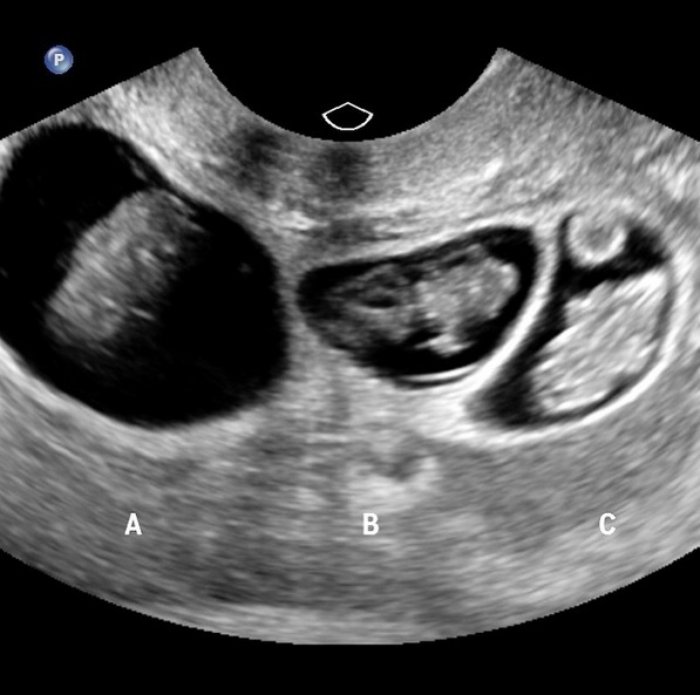

- Doktor kontrolünde yeni bir sürpriz ile karşılaşıyorlar: Üçüz çocukları olacağı ortaya çıkıyor!

Doktor kontrolünde yeni bir sürpriz ile karşılaşıyorlar: Üçüz çocukları olacağı ortaya çıkıyor!

Üçüzlerden ikisi yine erkek ama diğeri bir kız